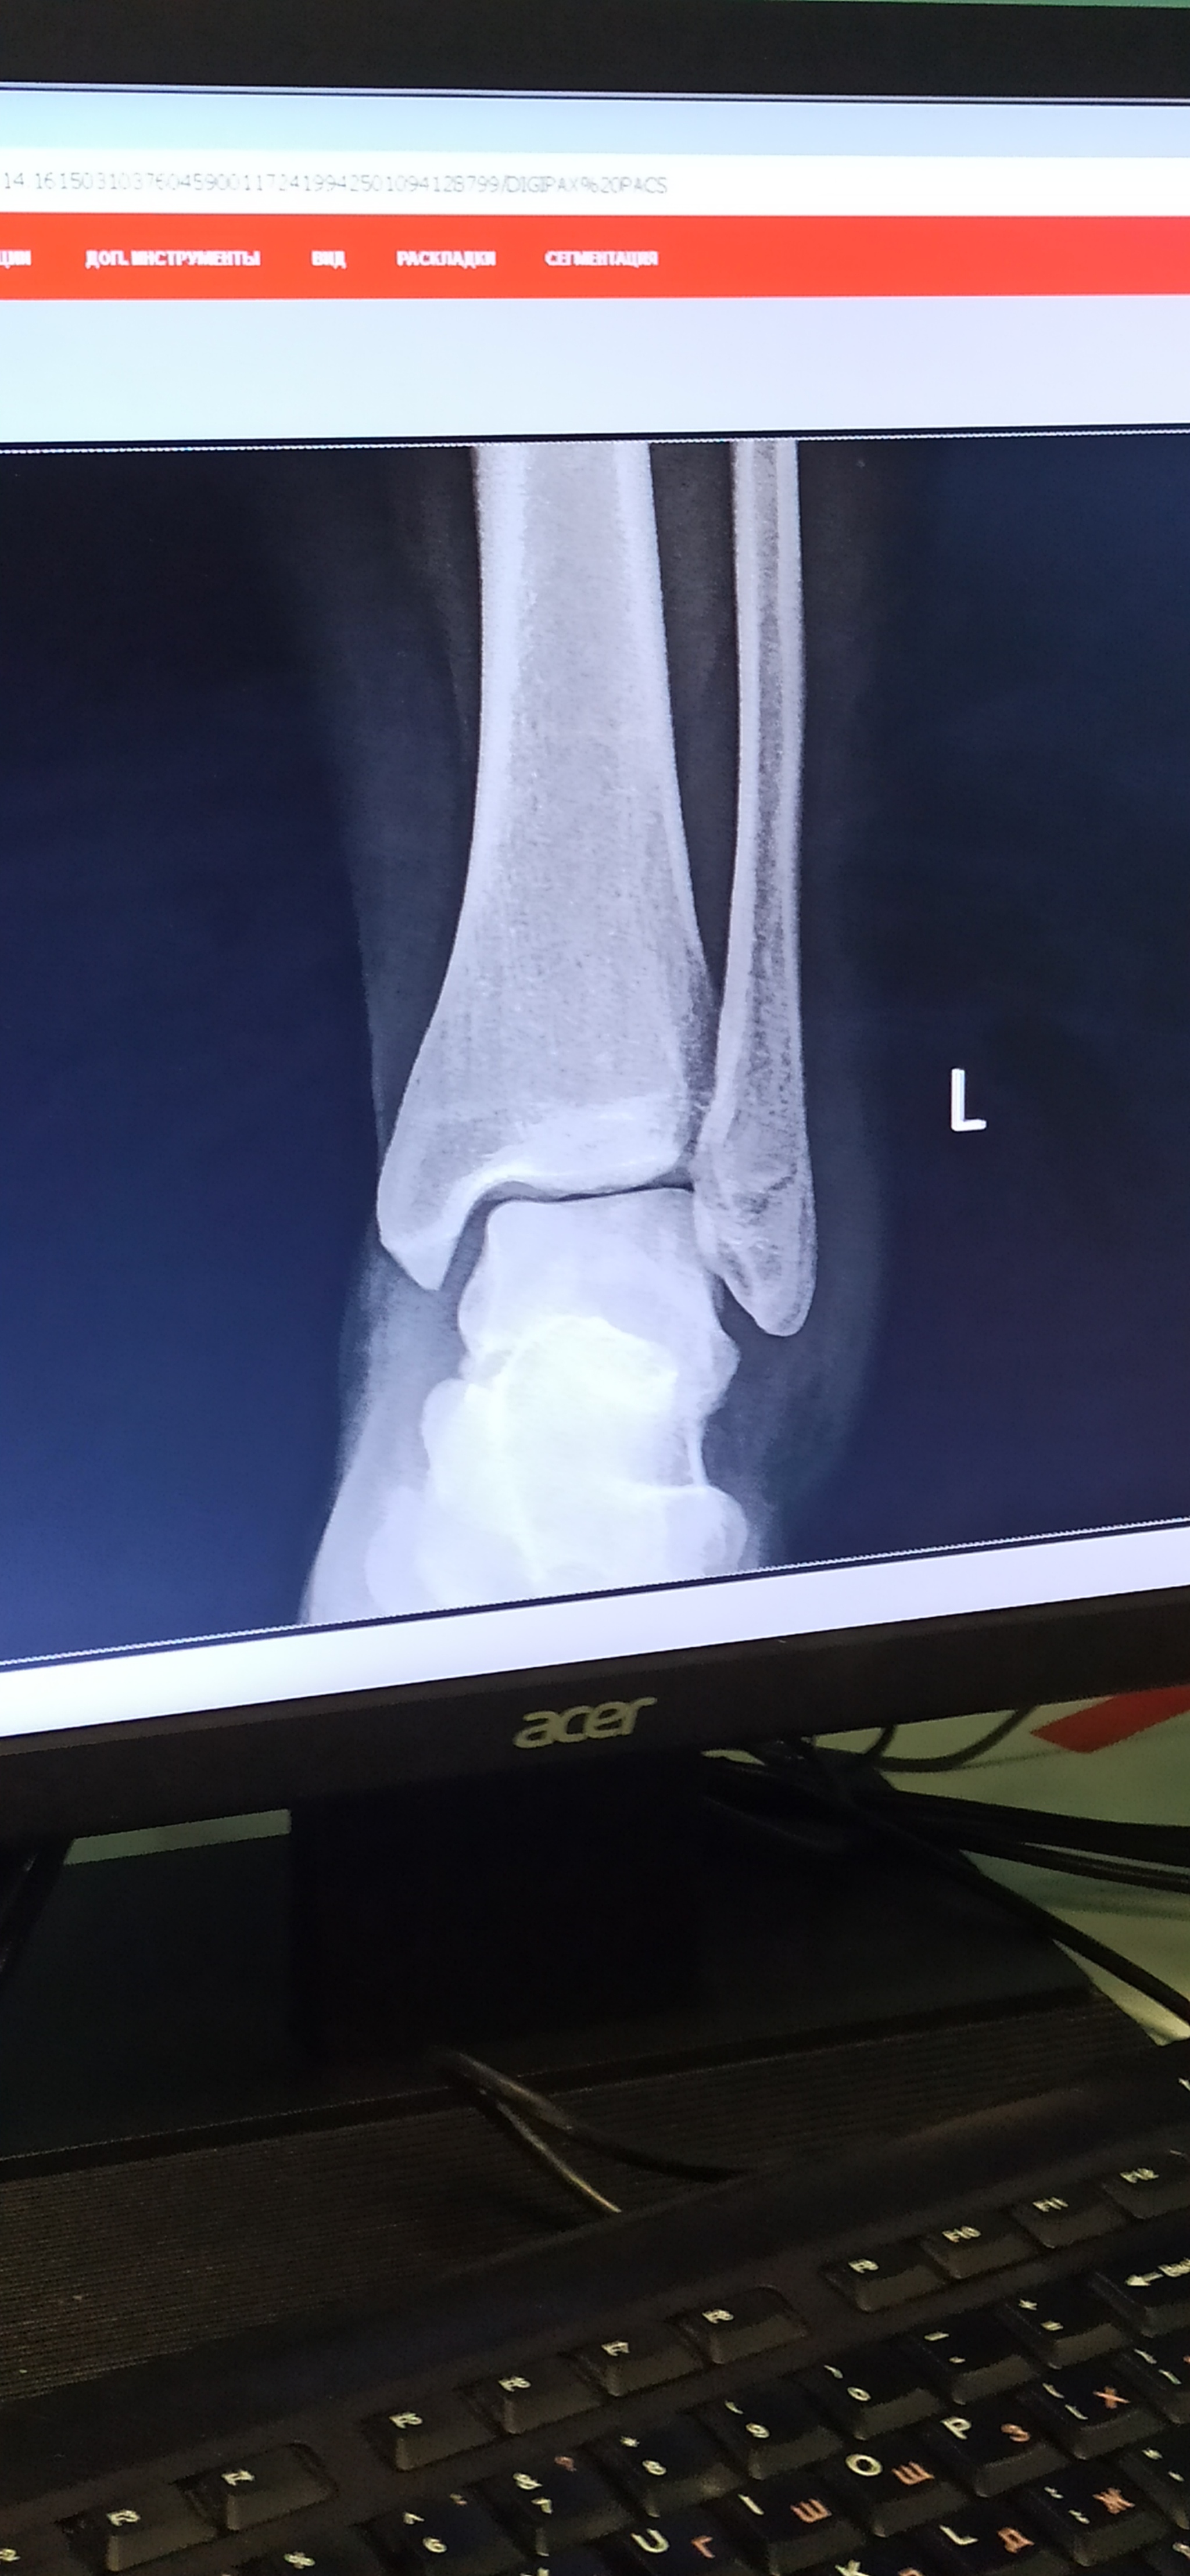

Поскользнулась (очнулась, гипс), закрытый перелом наружной лодыжки.

Пруфы, если надо. Ну мало ли, вдруг кто-нибудь дельного посоветует. И гипс буду менять.